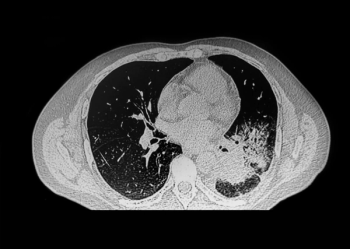

While a large retrospective study found that interstitial lung abnormalities (ILAs) were evident on 1.7 percent of computed tomography (CT) scans, researchers found that 43.9 percent of ILAs, including fibrotic ILAs, were not reported.

For patients undergoing curative treatment for lung cancer, coronary artery calcification scoring via computed tomography has a 97 percent likelihood of determining their risk for major cardiovascular events, according to a new meta-analysis.

New research demonstrates that photon-counting computed tomography angiography (PC CTA) provides sensitivity, specificity, and accuracy rates of 90 percent and higher for the detection of stenotic disease in patients with peripheral artery disease (PAD).